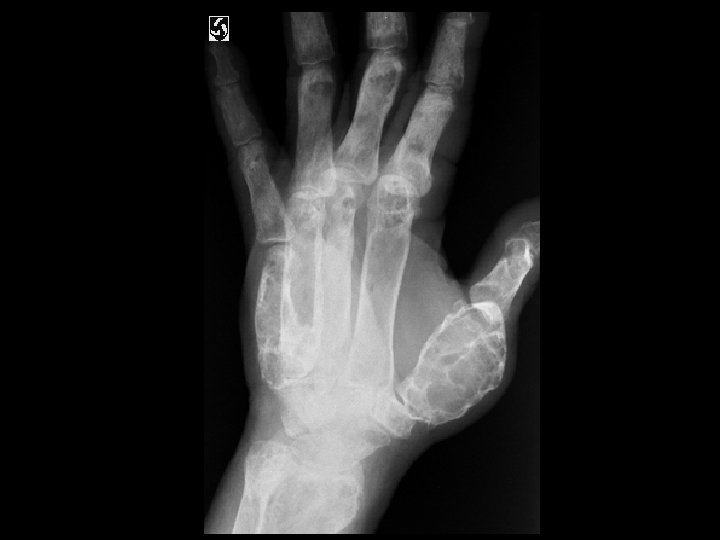

Tumoral Calcinosis • Findings: – Multiple dense calcifications around the joints of the fingers and wrists • ddx: (soft tissue Ca 2+) – Renal osteodystrophy – Heterotopic ossification – Metastatic Ca 2+ – Milk-alkali syndrome – Hypervitaminosis D – Scleroderma – Dermatomyositis